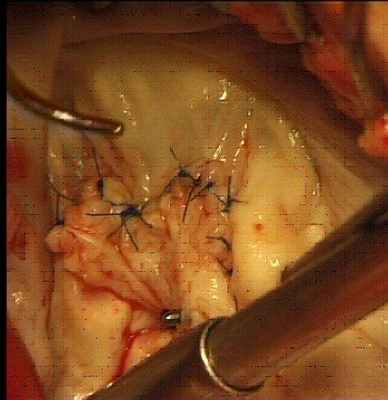

У 30-40% пациентов возможно выполнение реконструктивных операций на митральном клапане. Для этого используются различные методы реконструкции: аннулопластика на жестких и мягких кольцах, резекция створок, имплантация искусственных хорд, пластика «край в край». Восстановление нормальной функции митрального клапана у большинства пациентов в последующем не требует пожизненной антикоагулянтной терапии.

![]() |

Операции на митральном клапане выполняются как из стандартной стернотомии, так и из правосторонней миниторакотомии.